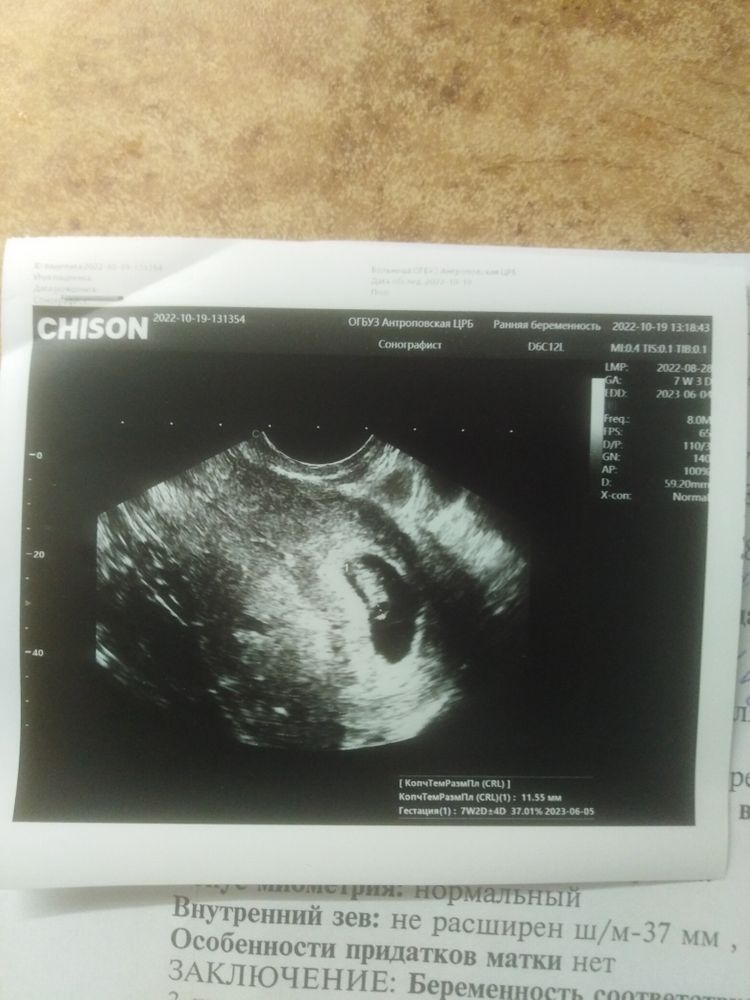

Ой, девочки, сходила на УЗИ. Наконец то!!!!!

Единственные не очень показатели 🌳Первый приём Гинеколога 🌳